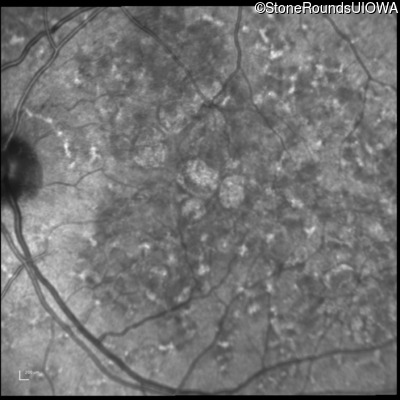

Blue Autofluorescence - Right - 20/20 -1 sc

Exemplar